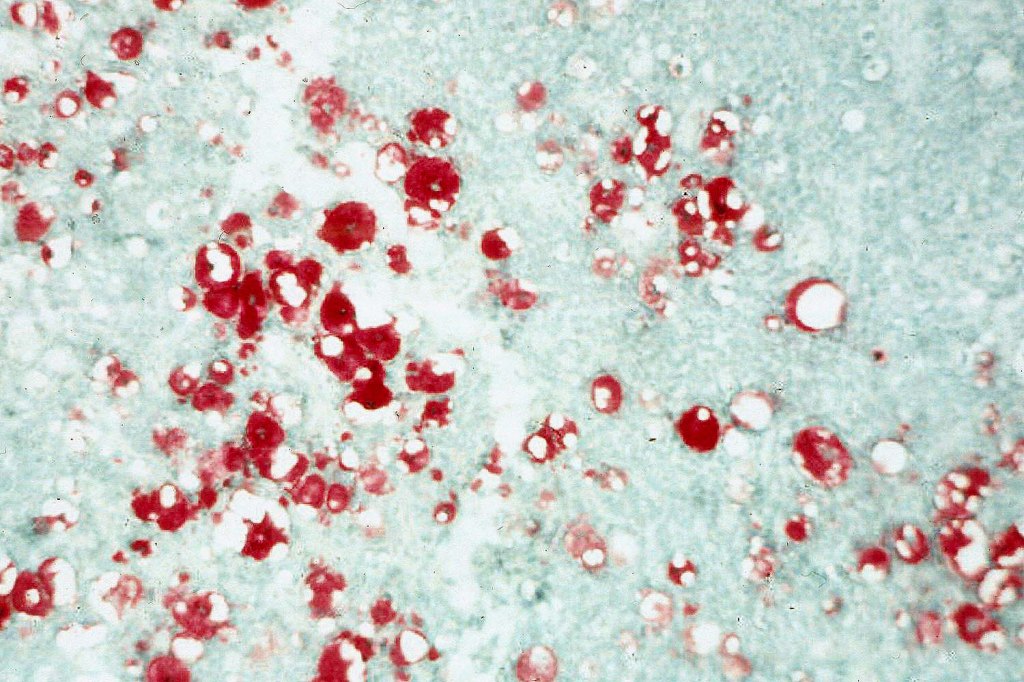

•Frozen section-stained tumor cell lipid can be highlighted with Oil Red O

Sebaceous carcinoma from a patient with Muir-Torre syndrome kindly shared by Dr. Antonina Kalmykova.

Immunohistochemistry (from the Muir-Torre patient except for EMA which was shared by Dr. Tsheri Dorji